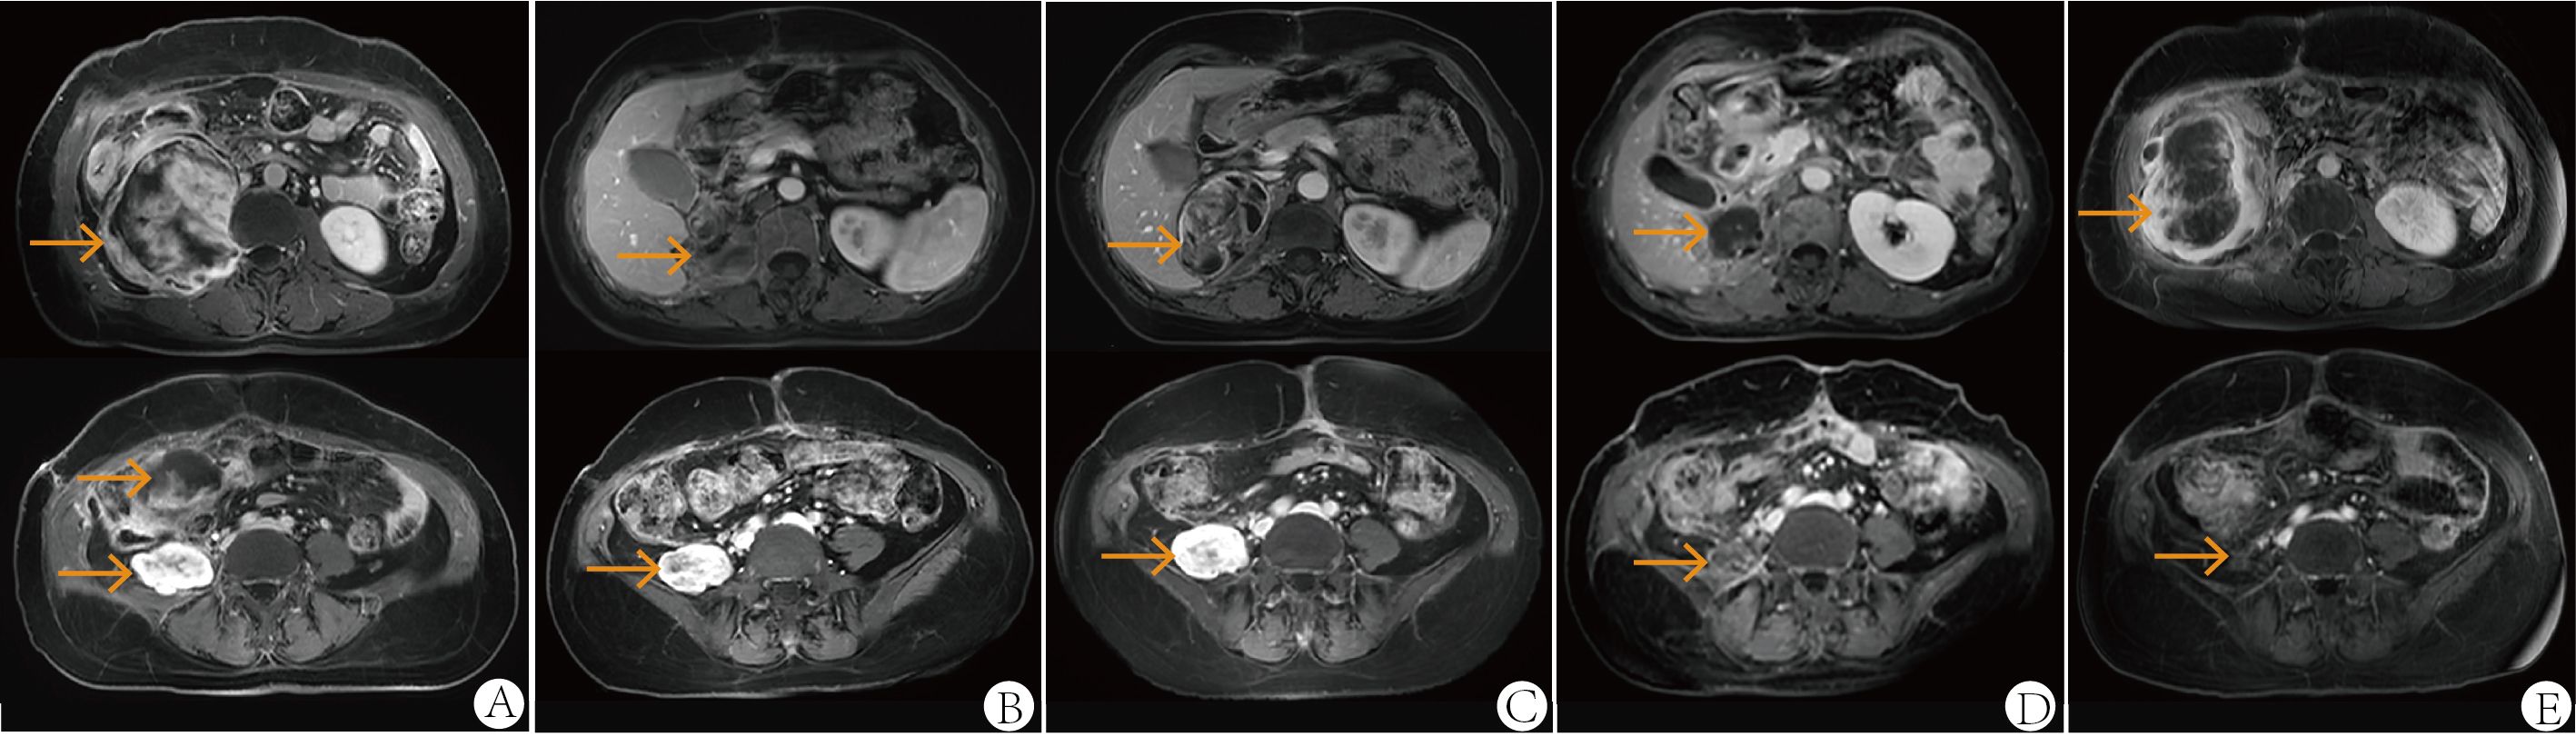

MRI scans of the abdomen in a two-by-five grid layout, each with orange arrows indicating specific areas. Different sections demonstrate various anatomical features and focal points on the scans. Panels A to E show distinct slices offering comparative views for medical evaluation.

Figure 2. Abdominal MRI at first relapse in October 2021 (A), one month after the second surgery in April 2022 (B), after two cycles of second-line therapy (gemcitabine plus albumin paclitaxel) in June 2022 (C), after six cycles of third-line therapy (eribulin plus sintilimab, combined with radiotherapy) in December 2022 (D) and at follow-up in June 2023 (E). All images were acquired with T1-weighted sequences.

Following the patient’s decision to pursue surgical intervention for the abdominal tumor, palliative cytoreductive surgery was performed. Intraoperatively, the tumor was found to be large and densely adherent to surrounding structures, necessitating extensive en bloc resection including the right kidney and right adrenal gland, partial repair of the abdominal aorta and inferior vena cava, limited repair of the colon and adhesiolysis. Final pathological evaluation confirmed an R1 resection margin. However, the MRI showed a rapid increase in tumor volume only one month after surgery (Figure 2B). The patient’s recovery from the second procedure was sufficient to permit the initiation of subsequent systemic therapy. In April 2022, the patient started second-line therapy of gemcitabine plus albumin paclitaxel. Unfortunately, the outcome was evaluated as PD after two cycles (Figure 2C). After a multi-disciplinary discussion, the patient was started on combination therapy of eribulin (2mg on days 1 and 8, every 3 weeks) and PD-1 inhibitor sintilimab (200mg, every 3 weeks) in June 2022. Concurrently, she underwent low-dose radiotherapy targeting the abdominal tumor. The radiation dose was escalated in coordination with immunotherapy and eribulin. A total dose of 54 Gy was delivered to the gross tumor volume in 18 fractions, covering the region from the upper border of the 11th thoracic vertebra to the lower border of the 5th lumbar vertebra (Figure 3). After six cycles of combination therapy, the tumor gradually decreased in size, achieving a partial response (PR) in December 2022 (Figure 2D). Treatment-related adverse events included fatigue, abdominal pain, leukopenia, neutropenia, thrombocytopenia as well as elevations in transaminases and uric acid, all graded as CTCAE Grade 1-2. Subsequently, the patient received maintenance therapy with sintilimab from December 2022, which effectively controlled all adverse events. Remission was sustained for 12 months. However, in June 2023, follow-up MRI indicated disease progression, accompanied by the gradual onset of abdominal pain (Figure 2E). Despite a rechallenge with eribulin, the disease progressed rapidly, and the patient declined further anti-tumor treatment. Regrettably, the patient succumbed to the disease in December 2023. Figure 4 illustrates the patient’s treatment course.